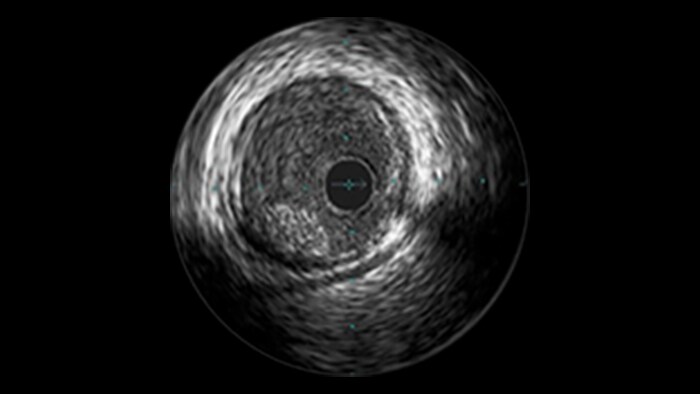

Approximately 20% of the coronary lesions treated today are long and diffuse.1,2

– Stent length is an independent predictor of in-stent restenosis and thrombosis.

– Stenting long segments with multiple and or overlapping stents may lead to injury to the vessel wall integrity.

– Diffuse CAD may be underestimated by evaluation with coronary angiography.

– Determining reference vessel sizing can be challenging when the vessel is diffusely diseased.